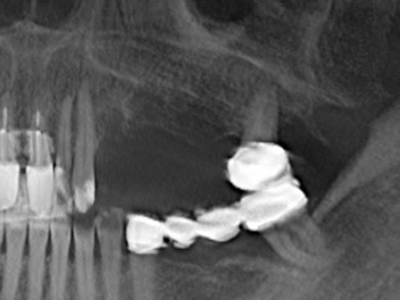

Fig. 11: El ortopantomograma posoperatorio presenta el aumento vertical y la elevación del suelo del seno.

Fig. 12: Después de seis meses de cicatrización se muestra una cresta maxilar vital con unas dimensiones suficientes en todas las direcciones.

Fig. 17: Tomografía computarizada de un osteoma de crecimiento progresivo ...

Fig. 17b: justo al lado del canal alveolar con irritación nerviosa (vista lateral y coronal).